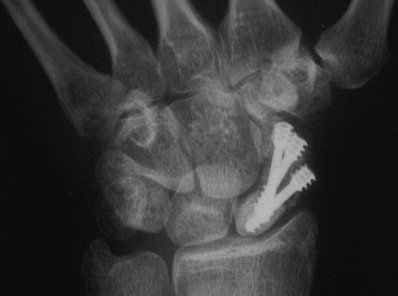

Case 8. Transscaphoid perilunate fracture dislocation...

Click for larger image

Two screws put in dorsally, LT ligament reinforced with a strip of extensor retinaculum left attached to the triquetrium and anchored into the lunate; temporary capitolunate pin.